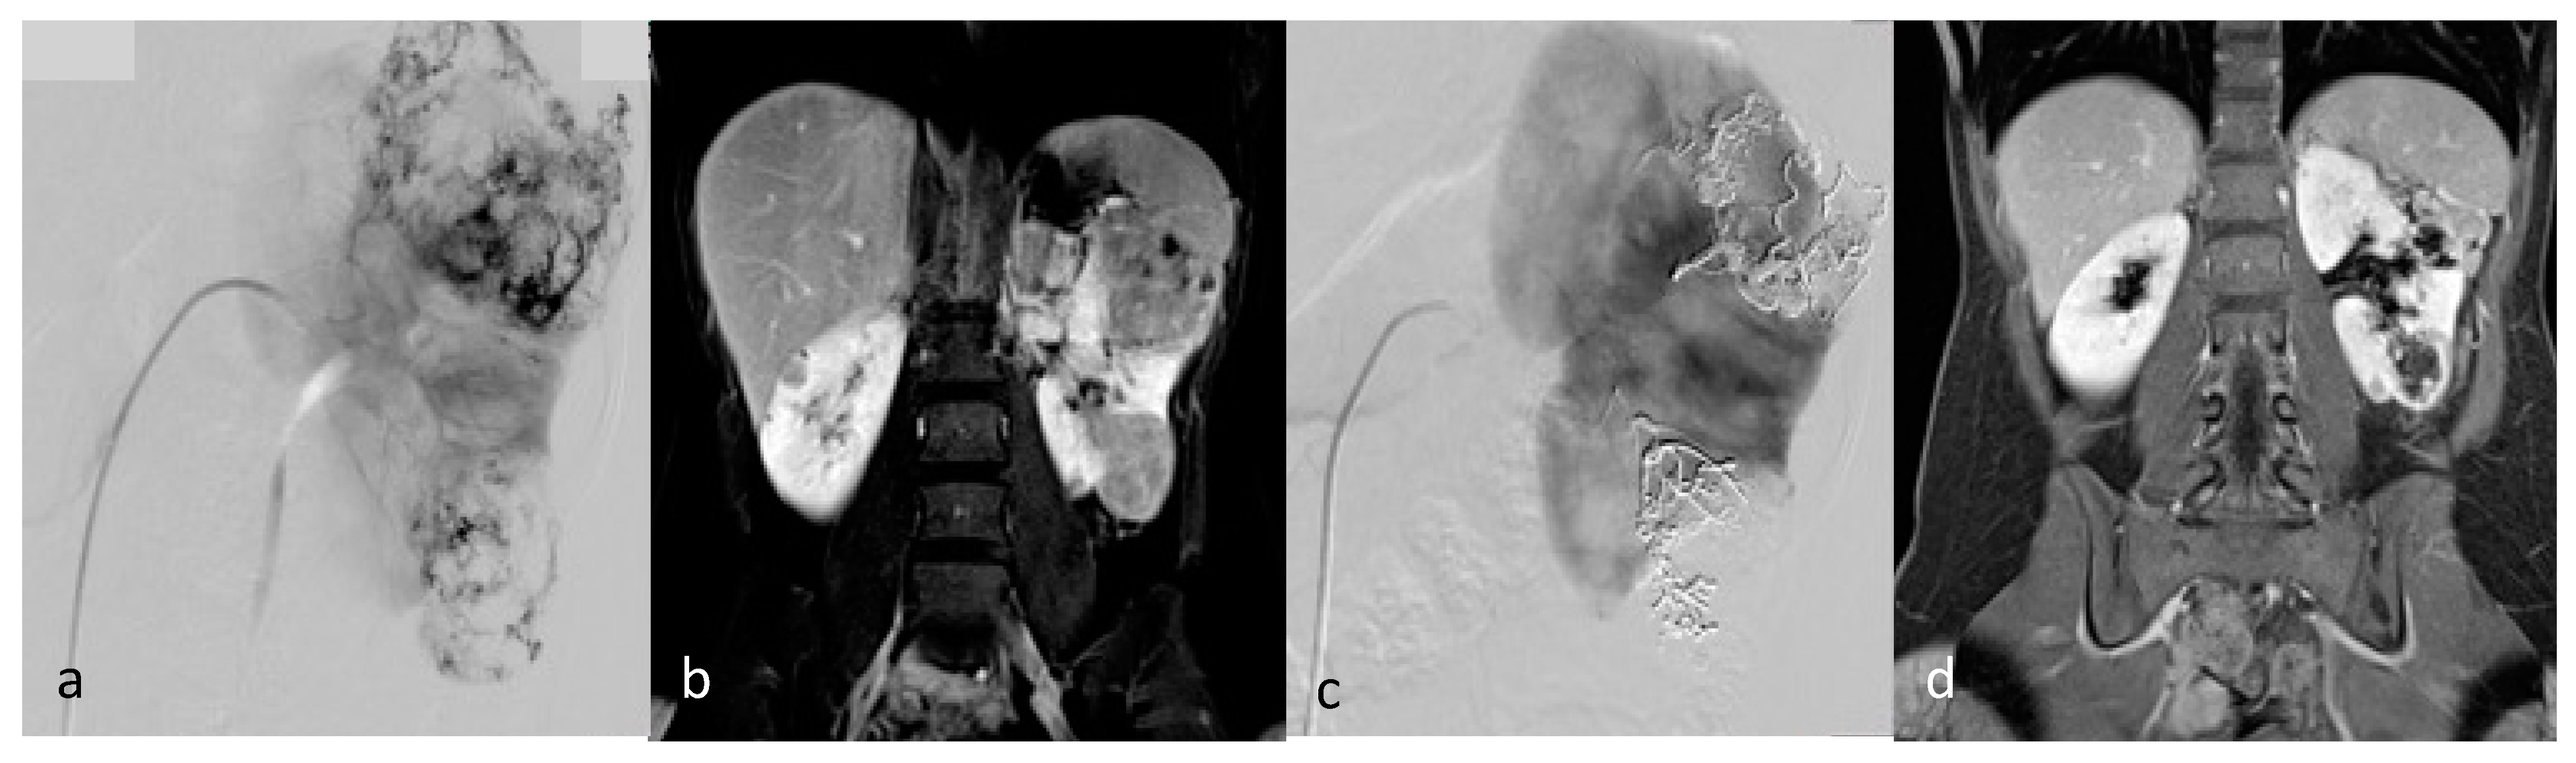

Figure 4.

Selective arterial embolization (TAE) of two large left AML. (a) Angiography shows two AML with dysplasic vascularization. (b) MRI showing the two AML on coronal T1 FatSat VIBE Sequence with Gadolinium with hyposignal T1 aneurysms before TAE. (c) Final angiographic control after TAE of the two arterial branches with ONYX 18 (6% EVOH) with technical success (lack of opacification of the AML) (d) MRI showing the two AML on coronal T1 FatSat VIBE Sequence with Gadolinium after TAE, with a volume shrinkage of 83 % for the upper one and 49% for the lower one.